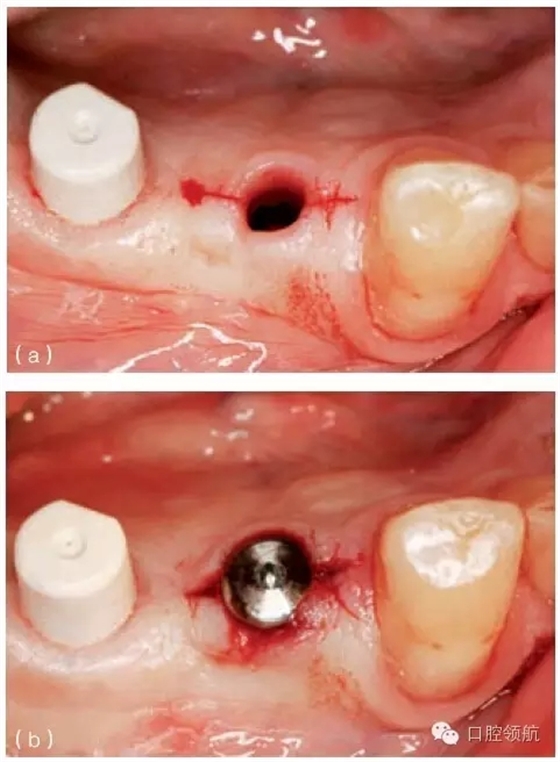

另外一個(gè)方面,深的袖口將妨礙修復(fù)體完全就位(圖9.26)。通常可以通過放射學(xué)檢查,確認(rèn)修復(fù)部件的就位情況,包括種植體與基臺(tái)的連接部分。即使是內(nèi)連接,轉(zhuǎn)移體或者其他修復(fù)部件也會(huì)因深袖口而不能就位。以下技術(shù)可以用于解決這些問題:可以在局部麻醉下,插入喇叭狀或者外展的基臺(tái),以非手術(shù)的方式擴(kuò)大袖口(圖9.27 a,b),然后再通過放射學(xué)檢查確定部件的完全就位。組織會(huì)受壓發(fā)白,15分鐘后,軟組織將會(huì)擴(kuò)張,以允許理想修復(fù)部件的就位,這樣治療將得以繼續(xù)。有時(shí),需要在鄰面做兩個(gè)小切口,以緩解袖口軟組織張力(圖9.28 a,b)。通常不需要縫合。一旦袖口組織塑形完成,可運(yùn)用最佳塑形的臨時(shí)(圖9.29)或最終部件(圖9.30),來維持理想的軟組織外形。

圖9.28 (a)做鄰面切口,使軟組織易于擴(kuò)張,以適應(yīng)外展的愈合基臺(tái)。(b)寬頸愈合帽就位,阻力很小。